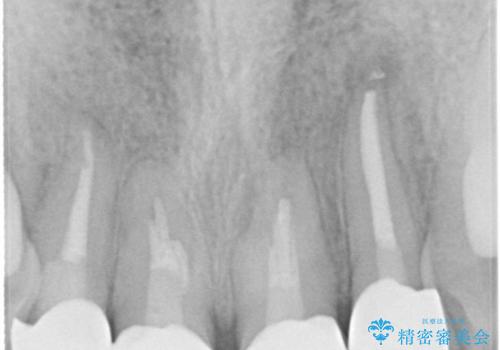

- 上の前歯の見た目が気になるとのことで来院されました。

上の前歯の4本が神経の処置がされており、前から2番目の歯が内側に入り込んでしまっていました。

また、金属で治療された根本の歯茎が黒く変色(メタルタトゥー)しており、余計に見た目がよくない状態となっておりました。

矯正治療で前歯の歯並びを整えてからセラミックほ装着する計画としました。